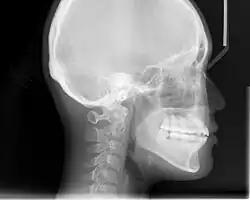

In the postwar period, cephalometric radiography[14] started to be used by orthodontists for measuring changes in tooth and jaw position caused by growth and treatment.[15] The x-rays showed that many Class II and III malocclusions were due to improper jaw relations as opposed to misaligned teeth. It became evident that orthodontic therapy could adjust mandibular development, leading to the formation of functional jaw orthopedics in Europe and extraoral force measures in the US. These days, both functional appliances and extraoral devices are applied around the globe with the aim of amending growth patterns and forms. Consequently, pursuing true, or at least improved, jaw relationships had become the main objective of treatment by the mid-20th century.[8]

An X-ray taken for skull analysis